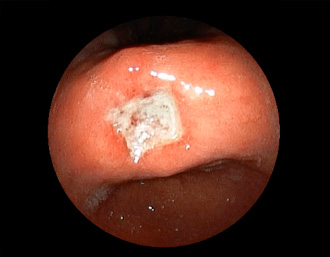

胃カメラ症例

当院で発見された症例の一部をご紹介致します。

胃潰瘍(37才、男性)

健診:胃レントゲン検査で、胃角部ニッシェを指摘され当院受診。

胃角部小弯に、深くて大きな、大きさ約10mmの胃潰瘍(stage 1)があり、潰瘍底は一部白苔はみ出しを認める。エソメプラゾールマグネシウム水和物投薬で治療開始しました。

通常画像

FICE画像